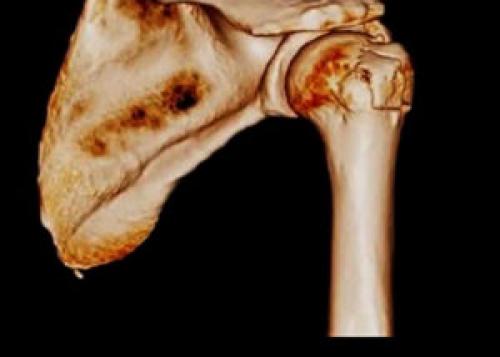

Остеосинтез плечевой кости реабилитация. Остеосинтез кости плеча

При сложных переломах с деформацией плеча, когда есть раздробление кости, правильным будет применение остеосинтеза плечевой кости. Эта операция проводится при невозможности совместить отломки поврежденного твердого органа. Вмешательство проходит под наркозом с применением винтов, штифтов и пластин, соединяющих костные отломки.

Остеосинтез: описание и особенности проведения манипуляции

Методика проведения

Есть два основных вида остеосинтеза: погруженный и наружный. При внутреннем (погруженном) методе используют различные импланты, которые закрепляют осколки кости внутри тела. В зависимости от характера перелома, это могут быть штифты, винты, пластины, спицы или металлические стержни. Соединение штифтом позволяет точно восстановить отколки и сохранить длину конечности. Остеосинтез пластиной применяется при переломе сустава со смещением. Она стабильно фиксирует кости, сводит к минимуму повреждение мягких тканей. При наружном методе части раздробленной кости соединяют с помощью внешней фиксации, используя аппарат Илизарова. Выбор методики остеосинтеза плеча будет зависеть от показаний для его применения, используемых металлоконструкций, дополнительной фиксации и последующей реабилитации.